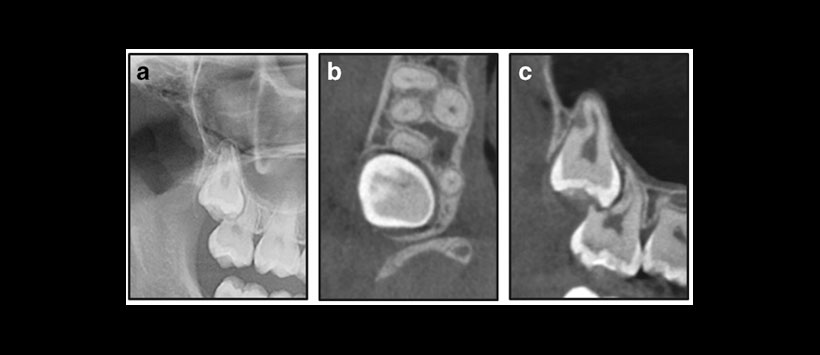

Para lo cual 111 terceros molares impactados, examinados clínicamente (incluyendo una panorámica), en 86 pacientes (edad media 26 años, rango 15-55) fueron remitidos para CBCT bajo sospecha de patología / reabsorción radicular en el segundo molar, según la información de la imagen panorámica. (Figura 1 y Figura 2)